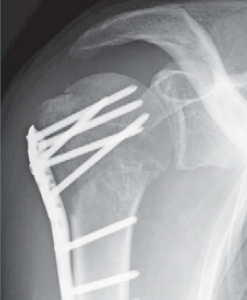

Hierbei werden unterschiedliche Implantate zur Stabilisierung des Knochenbruches in Abhängigkeit vom Frakturtyp verwendet. So können Frakturen entweder mittels Drähten, Schrauben, Platten oder Marknägeln stabilisiert werden.

Vielfach lassen sich teilweise auch komplexe Oberarmkopffrakturen minimal-invasiv versorgen. Dabei gelingt es über kleine Hautschnitte die verschobenen Fragmente wieder aufzurichten und mittels Humerusblock sowie zusätzlichen Schrauben die Fraktur zu stabilisieren (Abb. 53 bis 55). Neben der gewebeschonenden Versorgung stellt auch das günstige kosmetische Ergebnis einen entsprechenden Vorteil dar.

Ist durch die Schwere der Verletzung jedoch mit Hilfe dieser Implantate keine gelenkerhaltende Operation möglich, besteht die Möglichkeit des Oberarmkopfersatzes durch eine Prothese (künstlicher Teilgelenkersatz) (Abb. 56, 57). In den letzten Jahren wurden für diese Art des Gelenkersatzes spezielle Prothesenmodelle entwickelt, die sich individuell auf die Fraktur abstimmen lassen. So ist der Prothesenkopf höhenverstellbar, um frakturbedingte Höhenverluste auszugleichen. Des Weiteren besitzt die Frakturprothese besondere Vorrichtungen, um die abgerissenen Rollhügel (Tuberculum majus und minus) an der Prothese in anatomischer Position zu refixieren. Dies ist wichtig, da an den Rollhügeln die Sehnen der Rotatorenmanschette ansetzen und damit erst eine Funktion der Schulter wieder hergestellt werden kann.